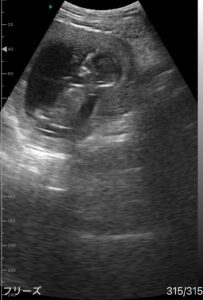

赤ちゃんはちょうど起きているタイミングだったのか、お腹の中で元気に跳ねたり回ったりと活発です。

その中でも特に目を引いたのが、まるでこちらに向かって手を振っているように見える瞬間でした。

その映像を仕事帰りのパパさんにも見せたところ「可愛い」と夫婦そろって口にしたそうです。